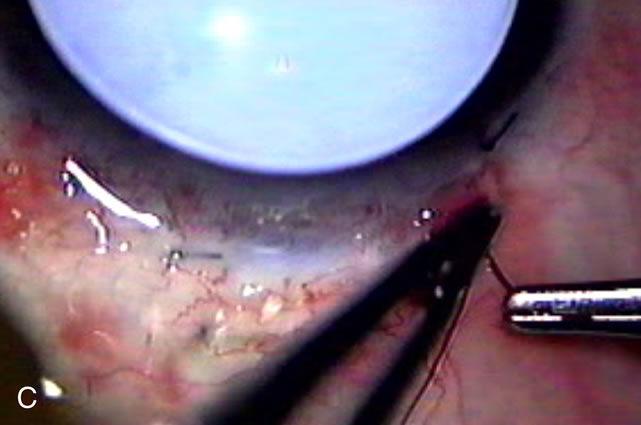

Fig. 3. Partial bleb failure following clear corneal phacoemulsification with foldable IOL. A. Preoperative bleb appearance prior to temporal lens extraction. Preoperative IOP was 12 mm Hg on no antiglaucoma medications. Time from 5-FU trabeculectomy surgery to lens extraction was one year. B. Bleb appearance 2 months after clear corneal cataract surgery with topical anesthesia. Following lens extraction, increased vascularity was noted along with decreased size of the filtering bleb. IOP increased to 20 mm Hg as early as 2 weeks after surgery, necessitating topical antiglaucoma therapy. C. High magnification view of bleb before lens extraction demonstrates diffuse pale bleb. D. High magnification view of bleb 2 months after surgery. There are vessels surrounding the nasal side of the bleb and the overall bleb size is smaller.